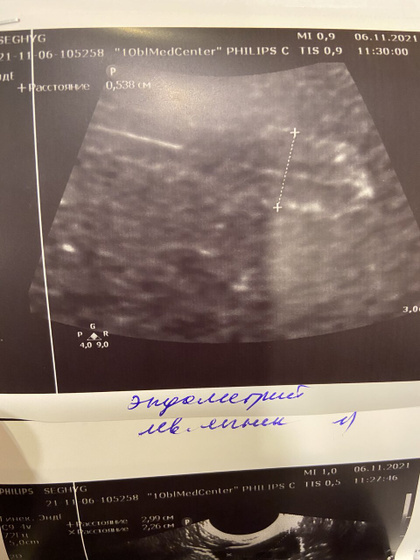

Сегодня была на узи, уже доминантный фолликул есть справа, овуляция дня через 3-4 примерно, начала делать тесты, НО, эндометрий снова тонковат(((( я прям очень переживаю за него, может из за его толщины не прикрепляется эмбрион? До последнего выкидыша никогда проблем не было с эндометрием! Верю что подрастёт ещё за несколько дней! Пожелайте удачи! ?